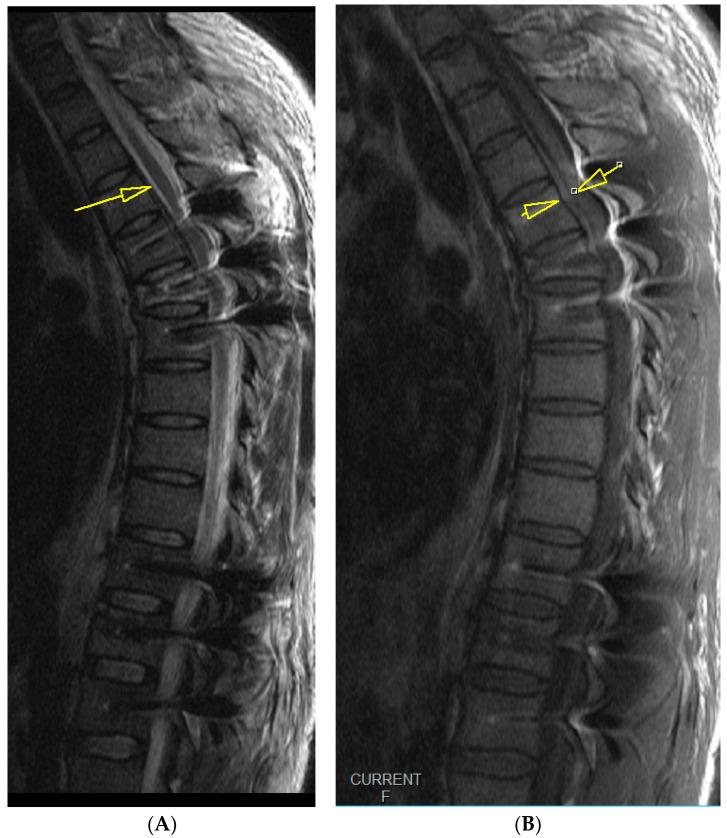

: Postoperative epidural hematomas of the cervical and thoracic spine can pose a great risk of rapid neurological impairment and sometimes require immediate decompressive surgery. : We present the case of a young patient operated on for stabilization of a two-level thoracic vertebra fracture who developed total paralysis due to an epidural hematoma postoperatively. The course of epidural hematoma was quickly reversed with the help of a conservative technique that prevented revision surgery. The patient regained complete neurologic function very rapidly, and has been well on every follow-up to date. : There is a role of similar maneuvers as described in this case to be employed in the management of postoperative epidural hematomas. However, prolonged watchful waiting should still be discouraged, and patients should remain ready for revision surgery if there are no early signs of rapid recovery.